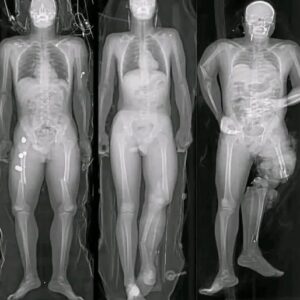

HT15. What you should know if you got the COVID vaccine: The truth behind these viral messages.

HT15. What you should know if you got the COVID vaccine: The truth behind these viral messages. In recent months, a wave of alarming images and short…